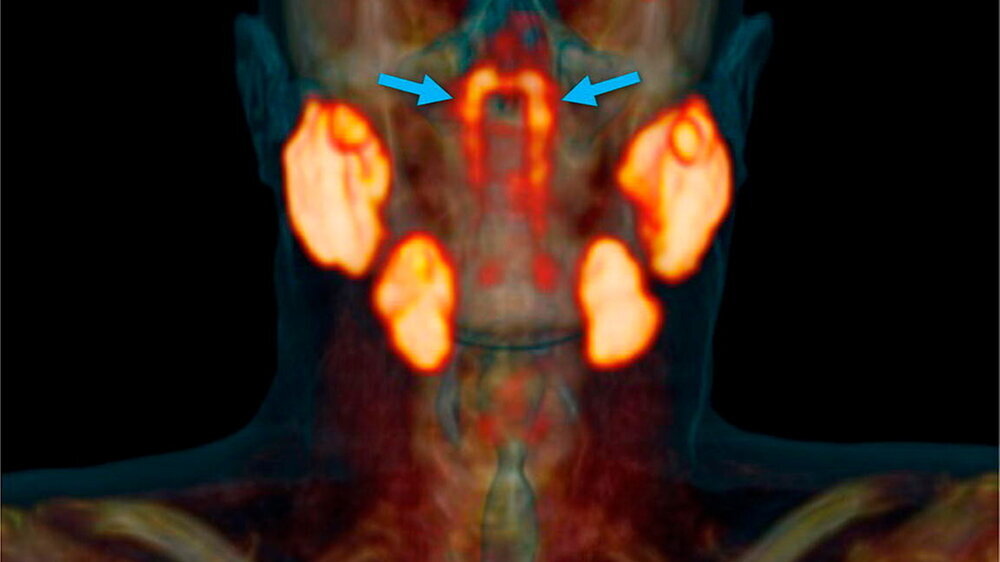

Bei dieser Drüse handelt es sich hingegen um Zellen mit einer Länge von 3,9 cm (Bandbreite 1,0 bis 5,7 cm) über den Torus tubarius, der das Mittelohr mit dem Rachen verbindet.

In Zusammenarbeit mit ihren Kollegen am UMC Utrecht entdeckten sie, dass alle 100 Personen, deren Scans sie wegen ihres Prostatakrebses untersuchten, einen Satz dieser Drüsen hatten. Histologie und 3-D-Rekonstruktion bestätigten das Vorhandensein von PSMA-exprimierenden, überwiegend schleimigen Drüsen mit mehreren Drainagekanälen, überwiegend in der Nähe des Torus tubarius.

Fazit der Wissenschaftler: Der menschliche Körper enthält ein Paar zuvor übersehener und klinisch relevanter makroskopischer Speicheldrüsenpositionen, für die sie den Namen Tubarialdrüsen vorschlagen. Wichtig ist die Schonung dieser Drüsen bei Patienten, die eine Strahlentherapie erhalten.